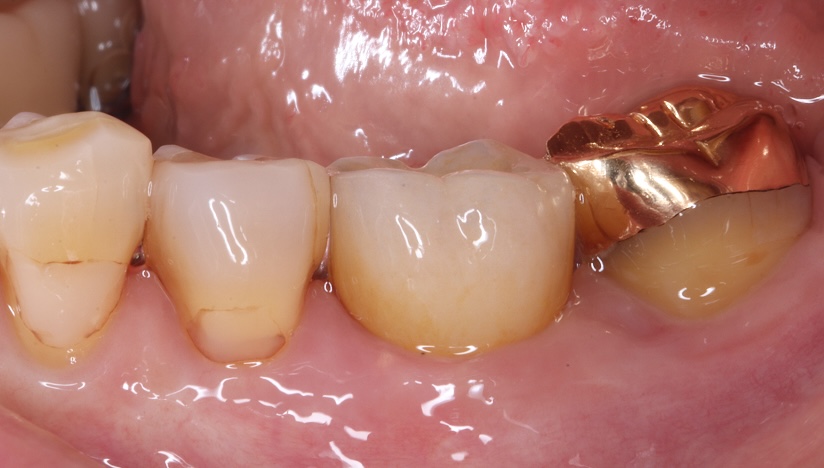

臼歯部(奥歯)単独インプラントで

他の天然歯を守った症例

主訴

噛むと痛い、歯茎が腫れてきた

治療内容

抜歯即時インプラント埋入、リッジプリザベーション(顎堤温存術)

治療期間

6〜8ヶ月

治療費用

649,000

治療の

リスク

オッセオインテグレーションが得られなかった場合、撤去、再度埋入の可能性